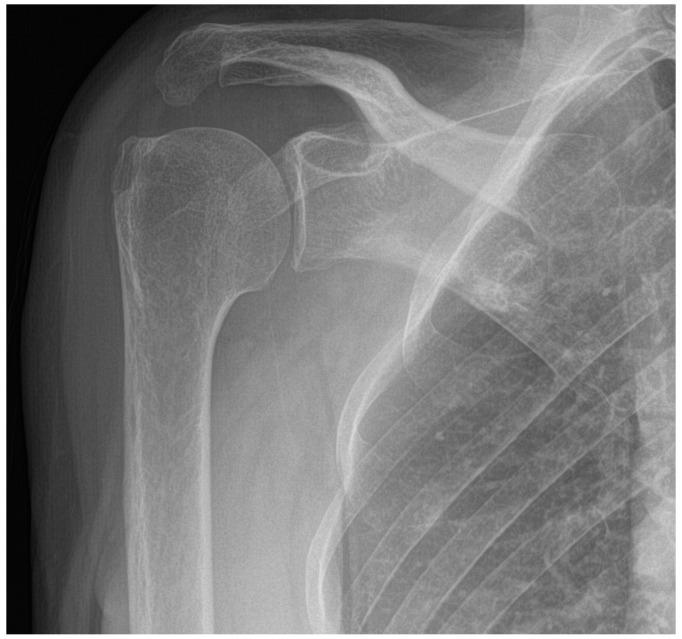

Chronic shoulder pain may cause significant functional disability and reduced psychosocial well-being. Detailed Case Description: In this case, we propose the use of pain neuroscience education and whole-body cryostimulation (WBC) to treat a 64-year-old woman with severe functional limitations and chronic right shoulder pain. The aim was to overcome kinesiophobia and improve her motor function, autonomy, and quality of life. Functional and clinical assessments were conducted at admission, discharge, and at a one-month follow-up via phone call. The patient's global health, shoulder function, and quality of life showed improvement during hospitalisation and were maintained after one month.

慢性肩部疼痛可能导致严重的功能障碍和心理社会幸福感下降。详细病例描述:在本病例中,我们建议使用疼痛神经科学教育和全身冷冻刺激(WBC)来治疗一名64岁的女性,她存在严重的功能受限和慢性右肩疼痛。目的是克服运动恐惧,改善她的运动功能、自主性和生活质量。在入院时、出院时以及通过电话进行的一个月随访时进行了功能和临床评估。患者的整体健康状况、肩部功能和生活质量在住院期间有所改善,并在一个月后得以维持。